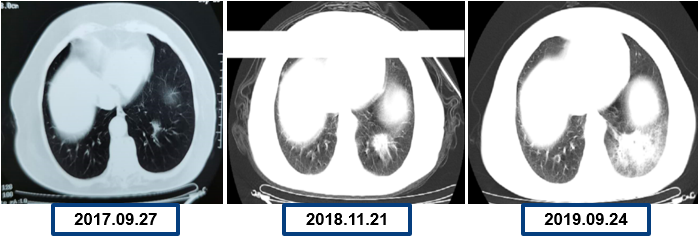

为提升肺癌前线免疫联合抗血管治疗的诊疗观念,学习与追踪肺癌领域诊疗最前沿知识,充分交流免疫/抗血管用药不良反应管理临床经验,【An例说】肺癌病例项目,征集大量临床高质量免疫联合抗血管治疗肺癌病例,并邀请全国各区域中青年及高职称医生与顶级TOP KOL互动发声!通过理念结合实践,研究结合病例,线上联动,共同促进学术由KOL/ROL向中青年医生下沉,为提升我国肺癌诊疗整体水平势在必行。免疫治疗的出现,对于晚期肺癌患者而言,显著提高了患者的生存质量及延长生存期,多项研究表明免疫治疗对于PD-L1表达阴性的患者也具有一定的治疗效果。为此,上海长海医院(海军军医大学第一附属医院)团队为您带来一例肺癌免疫联合抗血管病例分享。 患者,女性,78岁 2017年体检时发现左下肺结节,未行诊断及治疗。 2018.11.21、2019.09.24胸部CT均提示病灶较前变大,仍未诊治。 影像学检查 2020.01初逐渐出现胸闷、气短,活动后尤为明显。多次就诊于当地医院输液治疗(具体不详)。入院前2周胸闷,气急症状加重,无发热,无明显咳嗽,咳痰。2020.06.23入院。 影像学检查 既往史:高血压病30余年,最高血压170/90mmHg,规律服用美托洛尔12.5mg+利血平 0.1mg/日,自诉血压控制可。 个人史:无特殊 婚育史:无特殊 家族史:无特殊 T:37.0℃ P:104次/分 R:30次/分 BP:134/58mmHg 右肺及左肺可闻及湿罗音,左下肺呼吸音弱,无胸膜摩擦音。 心脏查体无异常。 入院后 CT引导下肺穿刺 穿刺后无咳嗽咯血,胸闷气急症状无加重。 6.25 出院等病理。 自行口服易瑞沙治疗,家中持续吸氧。 出院后3天突发病情变化: 6.28 凌晨1点左右,如厕后出现呼吸困难加重,晕倒。家属约2点发现,送至急诊,急诊予化痰、平喘、抗感染等对症治疗。 影像学检查 急诊检验检查: 【血气分析】PH 7.35、PO2 45.9mmHg、PCO2 62.6mmHg 【BNP】23.38pg/ml;【D-二聚体】0.32 【血常规】WBC:9.23×109/L、RBC:3.58×1012/L、HGB:98g/L、N%:80.2%、PLT:203×109/L。 【炎症指标】CRP:2.95mg/L;ESR:4mm/H;PCT:0.045ng/ml 【心电图】1. 窦性心动过速、2. ST-T异常。 血气分析 2020.06.29再次入院:左下肺腺癌、Ⅱ型呼吸衰竭、右肺阴影待查。 右肺渗出原因分析:感染?肿瘤进展?药物相关? 血常规变化: 选择治疗方案: 1. 两肺炎症,纵隔稍大淋巴结,炎症较2020.6.24进展,建议抗炎治疗后复查; 2. 左侧胸腔少许积液; 3. 两肺肺气肿、肺大泡,右肺中叶钙化灶; 4. 右侧第4肋骨皮质扭曲,请结合临床; 5. 甲状腺两侧结节,请结合超声。 右下肺腺癌 PD-L1无表达 抗血管生成与免疫联合的优点: 1、抗血管生成,靶点全面、强效抑制 2、抑制肿瘤细胞增殖和迁移,重塑肿瘤微环境,联合增效 3、肿瘤血管正常化及重塑,减轻免疫抑制状态 4、增加免疫效应细胞浸润 5、免疫刺激作用,激活免疫效应细胞 信迪利单抗联合安罗替尼的临床研究:这是一项前瞻性、非随机、三臂、Ib期临床研究。 临床研究试验设计 临床研究PFS和OS曲线 安罗替尼联合信迪利单抗一线治疗NSCLC,ORR达72.7%,DCR达100%,mPFS=15.6m,24m,OS率83.9%,表现出良好的治疗潜力。 派安普利单抗联合安罗替尼的临床研究:随机、双盲、多中心III期临床研究(NCT03866980) 临床研究试验设计 安尼可联合安罗疗效的ORR和DCR分析 数据截止日期:2021.1.13,共26例患者入组安尼可联合安罗替尼组,21例患者至少完成一次疗效评价。 帕博利珠单抗+安罗替尼 8mg。 治疗过程影像学检查 疗效评估: 2021.08.03: 疗效评估PR,截止目前PFS=15m。 该病例采用PD-L1抑制剂帕博利珠单抗联合小分子多靶点抗血管生成药物安罗替尼治疗老年肺腺癌患者,获得了15个月的PFS,提示对于驱动基因阴性,PD-L1无表达的晚期非小细胞肺癌患者免疫联合抗血管生成药物治疗是NSCLC患者一线治疗的选择和手段之一。 Impower150研究显示,贝伐珠单抗联合PD-L1抑制剂阿替利珠单抗+化疗显著改善了无突变非鳞NSCLC患者的PFS,中位OS达19.4个月(对照组14.7个月),ORR为71%。但治疗相关的毒副反应较大,一定程度上影响患者生活质量。小分子TKI联合免疫作为肿瘤去化疗联合治疗模式,越来越受到关注,前期探索性前瞻性随机临床研究包括信迪利单抗+安罗替尼(ACTION研究)、派安普利单抗+安罗替尼(AK105-301研究)和卡瑞利珠单抗+Apatinib/ target=_blank class=infotextkey>阿帕替尼(SHR-1210-III-315 研究)等一线治疗驱动基因阴性晚期NSCLC均得到了较好结果, 信迪利单抗联合安罗替尼组ORR达72%,DCR100%,中位PFS15.6个月,2年OS率83.9%,耐受性良好,显示出多靶点抗血管生成药物联合的良好应用前景。 免疫与抗血管生成药物以及与其他药物或方式联合该如何排兵布阵,肺癌治疗如何真正践行个体化和精准化,还有许多问题和挑战,有待进一步研究拓展和证实。 病例分享 焦洋 教授 上海长海医院,副主任医师,副教授 海军军医大学长海医院呼吸与危重症医学科 美国田纳西州大学附属医院呼吸与危重症医学科访问学者 上海市医学会呼吸分会感染学组秘书 中国老年医学会感染诊治与合理用药学术委员会委员 专业方向:疑难、复杂肺部感染及呼吸危重症的救治,肺癌的早期诊断和治疗。 专家点评 韩一平 教授 海军军医大学第一附属医院 呼吸与危重症医学科教授、主任医师 博士生导师 海军军医大学第一附属医院临床教育中心主任 中华医学会呼吸分会肺癌学组委员 中国医药教育协会肺部肿瘤专委会常委 中国医师协会全科分会委员,上海全科分会副会长 《中国肿瘤生物治疗杂志》《中国全科医学杂志》 《第二军医大学学报》《内科年鉴》等编委 获校“特级优秀教师”,上海市“育才奖” 首届上海“最美女医生” 主编发表教材或专著5部,近年发表文论50余篇 *仅供医学药学专业人士阅读 文章来源:ONCO前沿案例详情